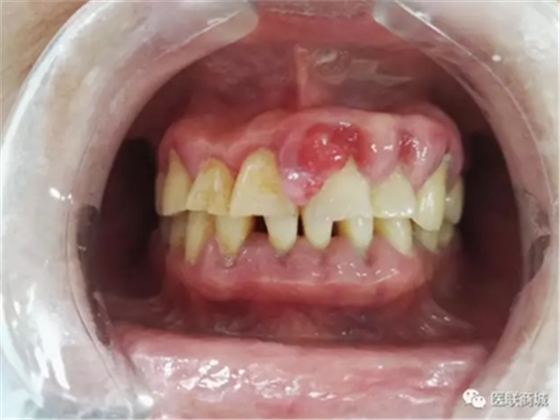

口腔衛(wèi)生狀況較差,牙石(++),軟垢(++),全口牙齦紅腫增生明顯,11、21、22、23牙齦增生明顯,11、21齦乳頭呈菜花樣增生,質(zhì)軟,界清,觸痛(-),易出血,全口PD=5-7mm,下前牙舌側GR=1-2mm,咬合關系基本正常,未見明顯咬合創(chuàng)傷。

曲斷示:全口牙齒牙槽骨水平吸收根長1/2-2/3。